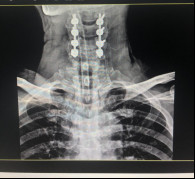

(術(shù)后拍片)

今年5月,張阿伯出院近2月后,大部分生活已經(jīng)可以自理。戈主任為張阿伯做了復(fù)查診治,結(jié)果顯示他的頸椎固定可靠,復(fù)位良好,病體正在朝理想的康復(fù)方向發(fā)展。